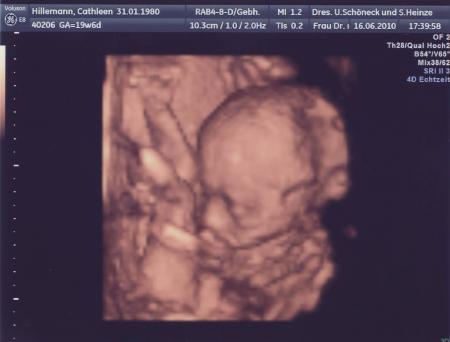

war zwar noch nicht zur fd, aber hab schon 2 tolle bilder bekommen, guckt ma, sieht aus, als ob er winkt, ne?

Bild zu